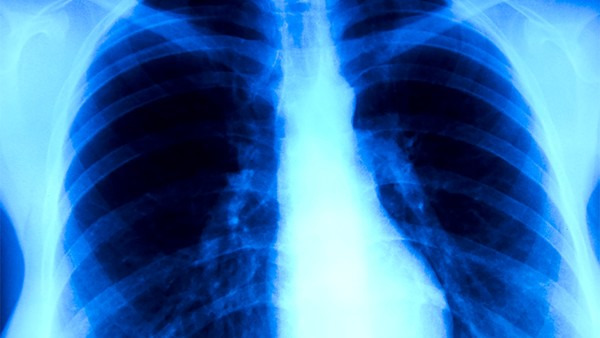

1.咳嗽。在早期的时候,一般不太明显,随着时间的增多,会导致患者有慢性支气管炎,还有的人会有肺部感染的情况出现。

2.咳痰。由于患者呼吸到粉尘,而没有及时清除而引起的。一般咳痰量不多,少数人会有黄色黏稠状或块状的痰,不容易咳出,十分难受。

3.胸痛。患者会感觉到胸痛,有的时候表现为针刺样痛。

4.呼吸困难。由于呼吸面积减少,而比例失调,就会导致呼吸困难。因此得了尘肺病,就要积极治疗。

5.咯血。这种现象不多见,一般是由于呼吸道炎症引起黏膜损伤,需要好好治疗。

6.其他。除了呼吸道以外,还会有程度不同的全身症状,比如消化功能减退等等。